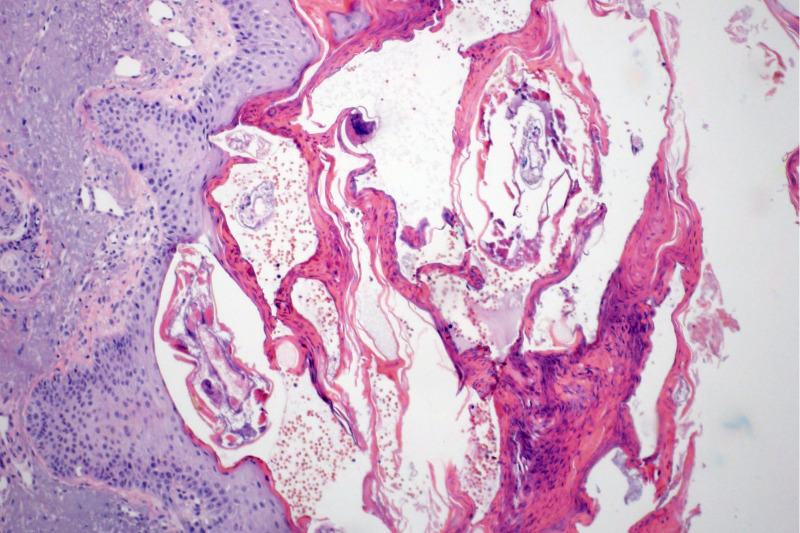

A Biópsia Simples: É uma  análise de fragmentos de tecido retirados por intervenção de pequeno porte (cirúrgica, endoscópica, com agulhas, raspados ou curetagem).

Imagem de Biópsias cirúrgicas simples